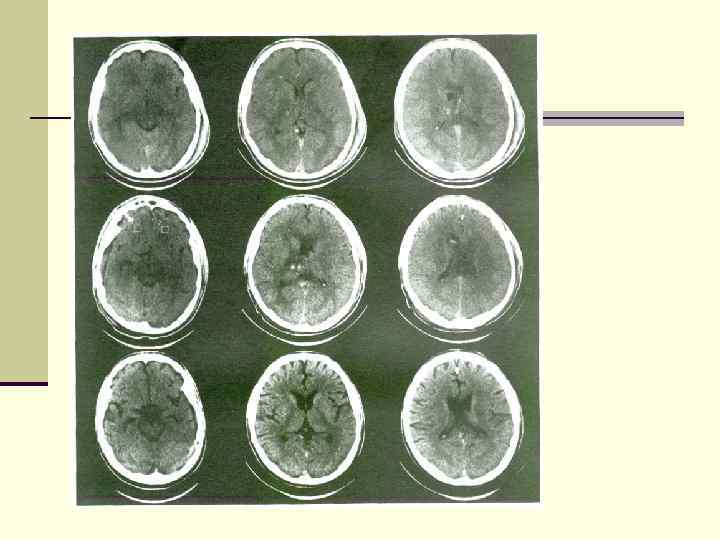

Локализация интрацеребральных кровоизлияний Локализация интрацеребральных кровоизлияний